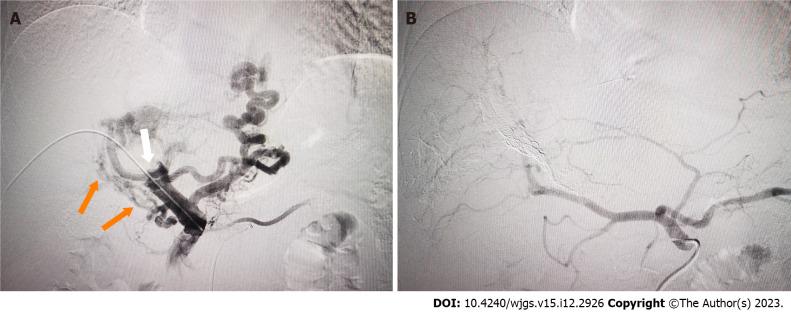

This case report describes a novel strategy of embolization of the portal venous outlet to reduce IHS and HPS caused by marked APS before TARE in a patient with advanced hepatocellular carcinoma (HCC). The patient had a significant intratumoral shunt from the tumor artery to the portal vein and had already been suspected based on pre-interventional magnetic resonance angiography, and digital subtraction angiography (DSA) confirmed the shunt. Selective right portal vein embolization (PVE) was performed to close the APS outlet and DSA confirmed complete closure. Technetium-99m macroaggregated albumin was administered and single photon emission computed tomography revealed a low HPS with 8.4%. Successful TARE was subsequently performed. No major procedure-related complication occurred.

本病例报告描述了一种新的策略,即在一名晚期肝细胞癌(HCC)患者中,在TARE之前栓塞门静脉出口以减少由显著APS引起的IHS和HPS。该患者存在从肿瘤动脉到门静脉的显著瘤内分流,在介入前磁共振血管造影时就已怀疑,数字减影血管造影(DSA)证实了分流。进行了选择性右门静脉栓塞(PVE)以封闭APS出口,DSA证实完全封闭。给予锝-99m大颗粒白蛋白,单光子发射计算机断层扫描显示HPS较低,为8.4%。随后成功进行了TARE。未发生重大的与手术相关的并发症。